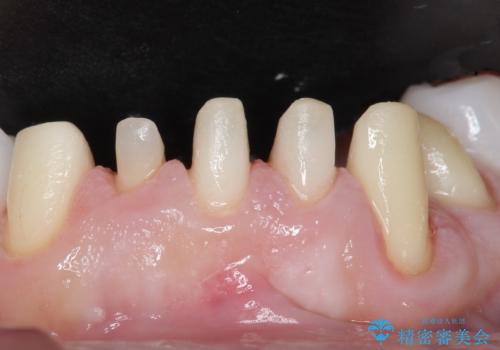

歯頚ラインが変えられないことや天然歯を削るリスクをご理解頂いた上で、オールセラミッククラウンによる補綴治療を行いました。(見えない奥歯のみ天然歯のままとしました)

下の前歯1本だけ歯軸を変えるために神経をとり根管治療を行っております。

それ以外の歯は神経をとらずに済むよう、慎重かつ丁寧に歯の形態を整えました。

クラウンの色味に関して、自然な白さ(シェードA1~NW0.5)のクラウンを作製・試適したところ「もっと白くしたい」と希望され、当院で最も明度の高い色(シェードNW0)に修正しました。

被せ物の種類:オールセラミッククラウン スタンダード (シェード:NW0)